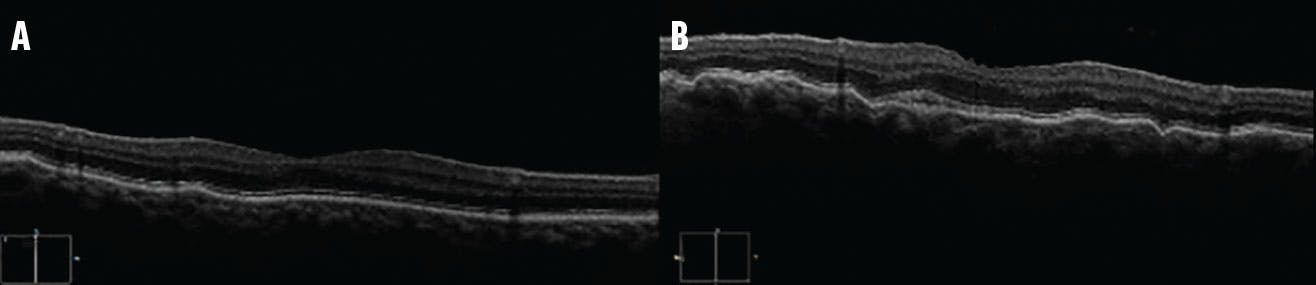

OCT revealed characteristic undulations of the RPE consistent with choroidal folds (Figure 3). Fluorescein angiography (FA) highlighted the choroidal folds in each eye (Figure 4). ICG did not reveal any choroidal masses (Figure 5), and a CT of the orbit was within normal limits. Blood workup was unremarkable.

<p>Figure 3. OCT of the right (A) and left (B) eye showed the characteristic undulations of the RPE consistent with choroidal folds with a nearly flat retinal surface and a variable retinal thickness.</p>

Figure 3. OCT of the right (A) and left (B) eye showed the characteristic undulations of the RPE consistent with choroidal folds with a nearly flat retinal surface and a variable retinal thickness.

OCT is the most specific imaging tool to detect and distinguish idiopathic choroidal folds from other etiologies, such as epiretinal membrane.10 FA is the most sensitive imaging modality, where choroidal folds usually present as alternating hypofluorescent and hyperfluorescent bands due to rarefaction and redundancy of the RPE at the folds’ peaks and pits, respectively.10 On ICG, a delay in the choroidal vessel filling has been reported in cases of choroidal folds caused by orbital tumor.10